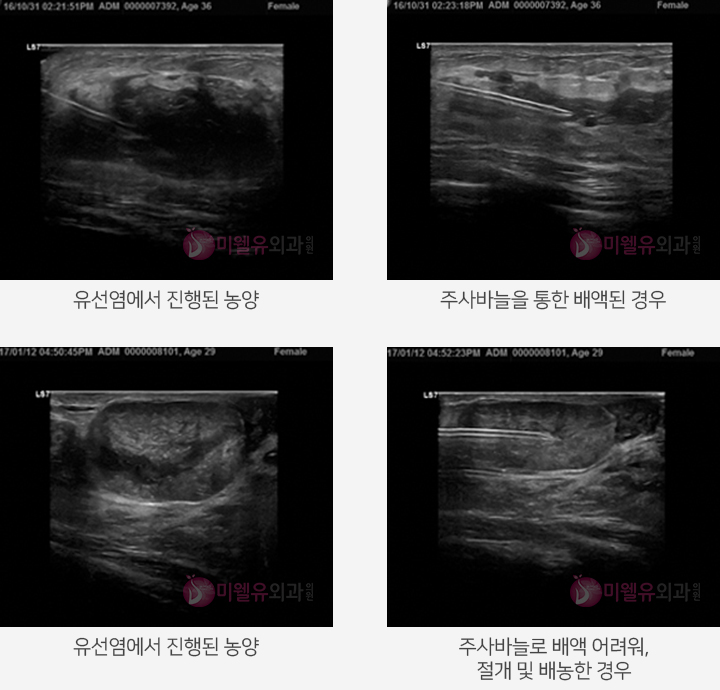

유선염이 진행되면 유방농양으로 진행될 수 있습니다.